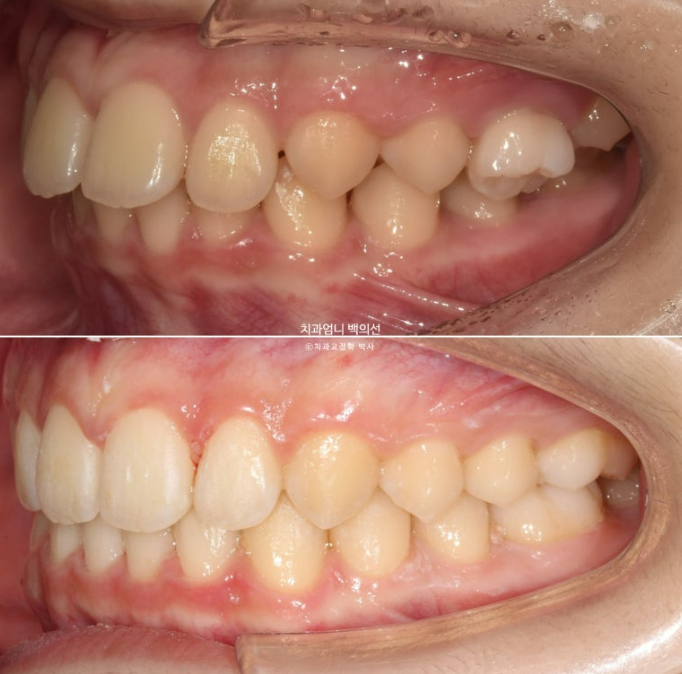

24.03~25.05

25년 5월 두번째 세트 21개 장치를 모두 낀 후 드디어 치료를 마무리 했습니다.

25.05

앞니 깊게 물리는 과개교합은 해결이 되었고 중심선은 잘 맞습니다.

어금니 교합은 1급 교합관계입니다.